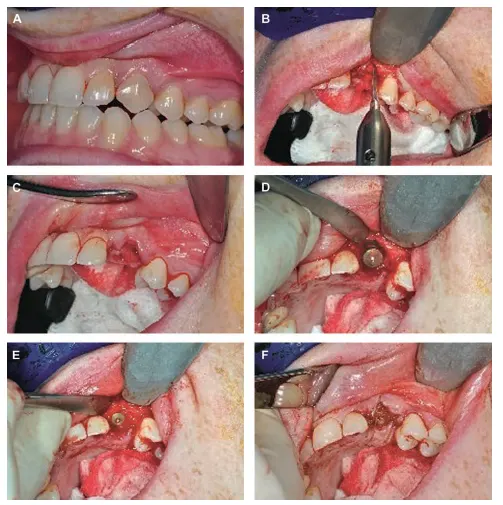

Immediate postextraction placement of implant شکل VIII‑2. کاشت ایمپلنت بلافاصله پس از کشیدن دندان

A: سگ‌دندان سمت چپ فک بالا پیش از کشیدن به‌دلیل شکستگی و تحلیل ریشه.

B: کشیدن آتروماتیک با استفاده از پریوتوم انجام شده است که منجر به حداقل از دست رفتن بافت نرم و استخوان شده است.

C: نمای محل کشیدن دندان.

D: ایمپلنت در محل کشیدن دندان قرار داده شده؛ تماس آپیکال دقیق با استخوان وجود دارد، اما شکاف کوچکی میان بخش فوقانی ایمپلنت و کرست محل مشاهده می‌شود.

E: ترمیم شکاف با استفاده از استخوان خشک‌شده منجمد (Freeze‑Dried Bone).

F: قرار دادن غشاء کلاژن قابل‌جذب روی ایمپلنت و پیوند، تثبیت‌شده با بخیه کرومیک قابل‌جذب. (شکل در ادامه صفحه بعد.)